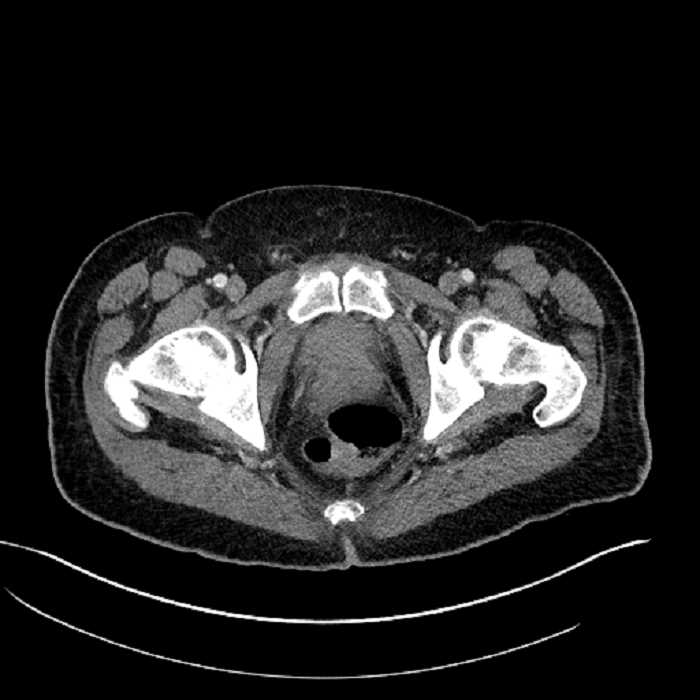

Age: 63

Sex: Male

Indication: Abdominal pain

• High grade stenosis of the left common iliac artery, with the left internal and external iliac arteries remaining patent

• Ankylosis of both sacroiliac joints

Acute sigmoid diverticulitis complicated by a small contained perforation and a large abscess in the right hepatic lobe. Additional small subcapsular abscesses along the anterior margin of the left hepatic lobe.

High grade stenosis of the left common iliac artery. The left external and internal iliac arteries are patent.

Hepatic abscess showing the double target sign with low density internally surrounded by a thin inner enhancing rim (red arrow) and ill-defined outer low density rim (yellow arrow). Blue arrow indicates an internal septation. Red arrows: additional smaller subcapsular abscesses. Red arrow: focal contained perforation associated with diverticulitis.